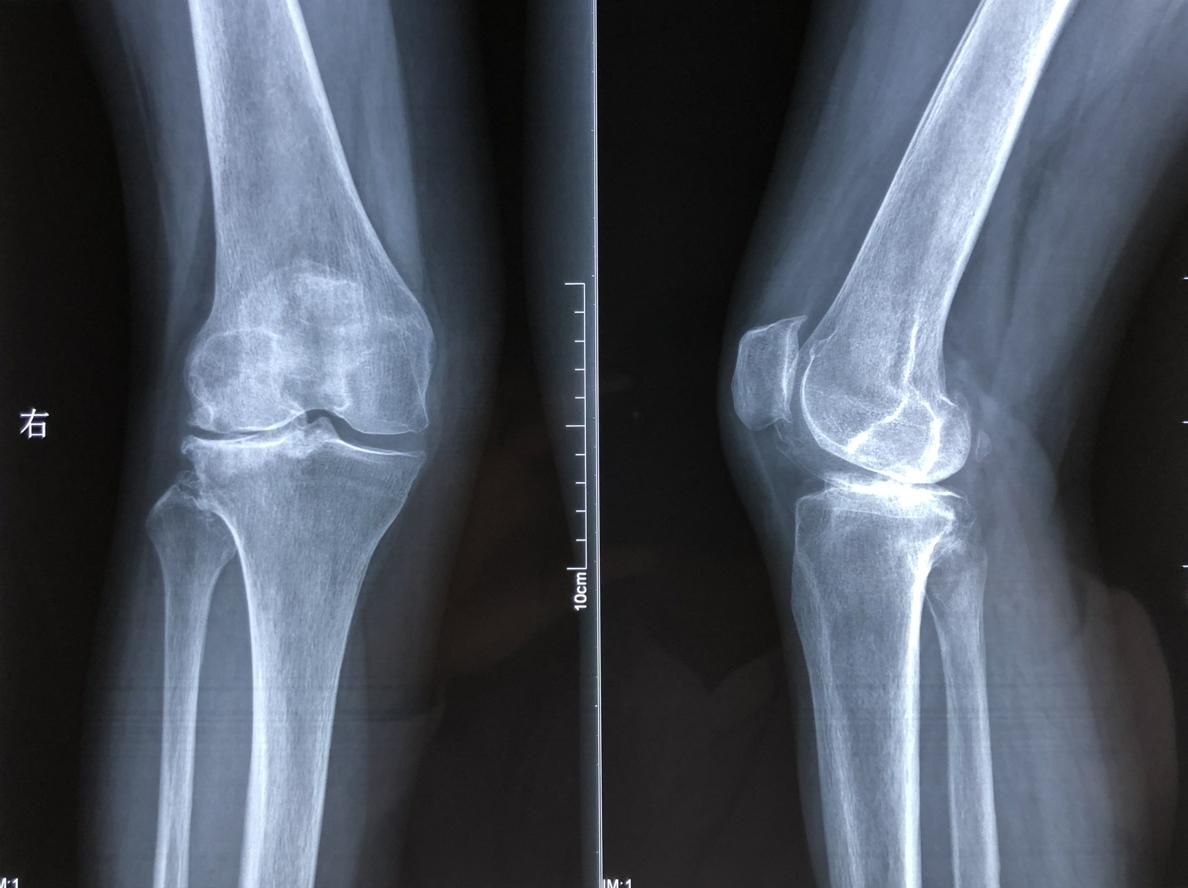

膝关节骨性关节炎

膝关节骨性关节炎(简称膝骨关节炎)是一种退行性关节疾病,核心是膝关节软骨磨损、骨质增生,导致关节疼痛、僵硬、活动受限,俗称 “老寒腿”“骨刺”。其发病与年龄增长(软骨自然退变)、肥胖(膝关节负重增加)、外伤史(如骨折、韧带损伤)、长期劳损(过度行走、爬楼)、遗传因素相关。

:关节肿胀、压痛,活动时可能听到 “摩擦音”,晚期可能出现关节畸形(如 O 型腿、X 型腿)。